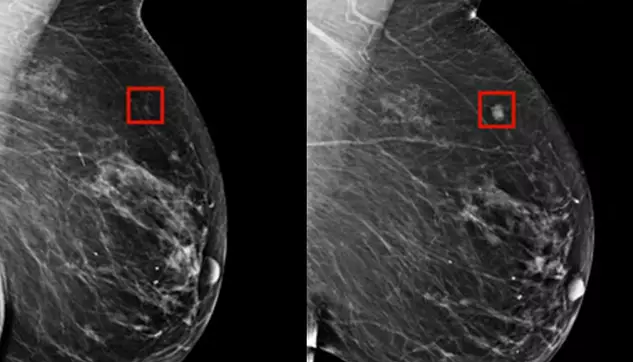

Ungarische Ärzte haben ein Modell der künstlichen Intelligenz eingesetzt, das als computergestützte Erkennung bezeichnet wird, und es gelang ihnen, einen Brustkrebs vier Jahre vor dessen Entstehung zu erkennen.

Die so genannte computergestützte Erkennung identifiziert Flecken in Mammographien, die die Ärzte genau untersuchen müssen. In einer MIT-Studie wurde festgestellt, dass die Technologie in der Lage ist, Veränderungen zwischen Mammogrammen zu erkennen und Flecken zu entdecken, bei denen das Risiko besteht, dass sie sich zu Krebs entwickeln. Die erkannten Stellen entwickelten sich erst Jahre später zu Brustkrebs.